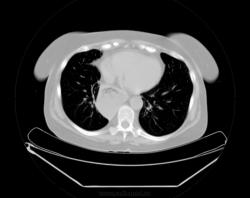

При профилактическом исследовании у женщины 75 лет выявлены изменения в легких и средостенье. Выполнена КТ. Ваше мнение, коллеги?

Почему провокация?! У меня что, имидж такой? о провокациях я так сразу и пишу в заголовке... Нет здесь ни провокации, ни загадки. Действительно, ахалазия кардии, пневмофиброз в легких, по-видимому метатуберкулезный. А случай мне показался интересным, потому как эта ахалазия имеет 50 лет анамнеза без лечения